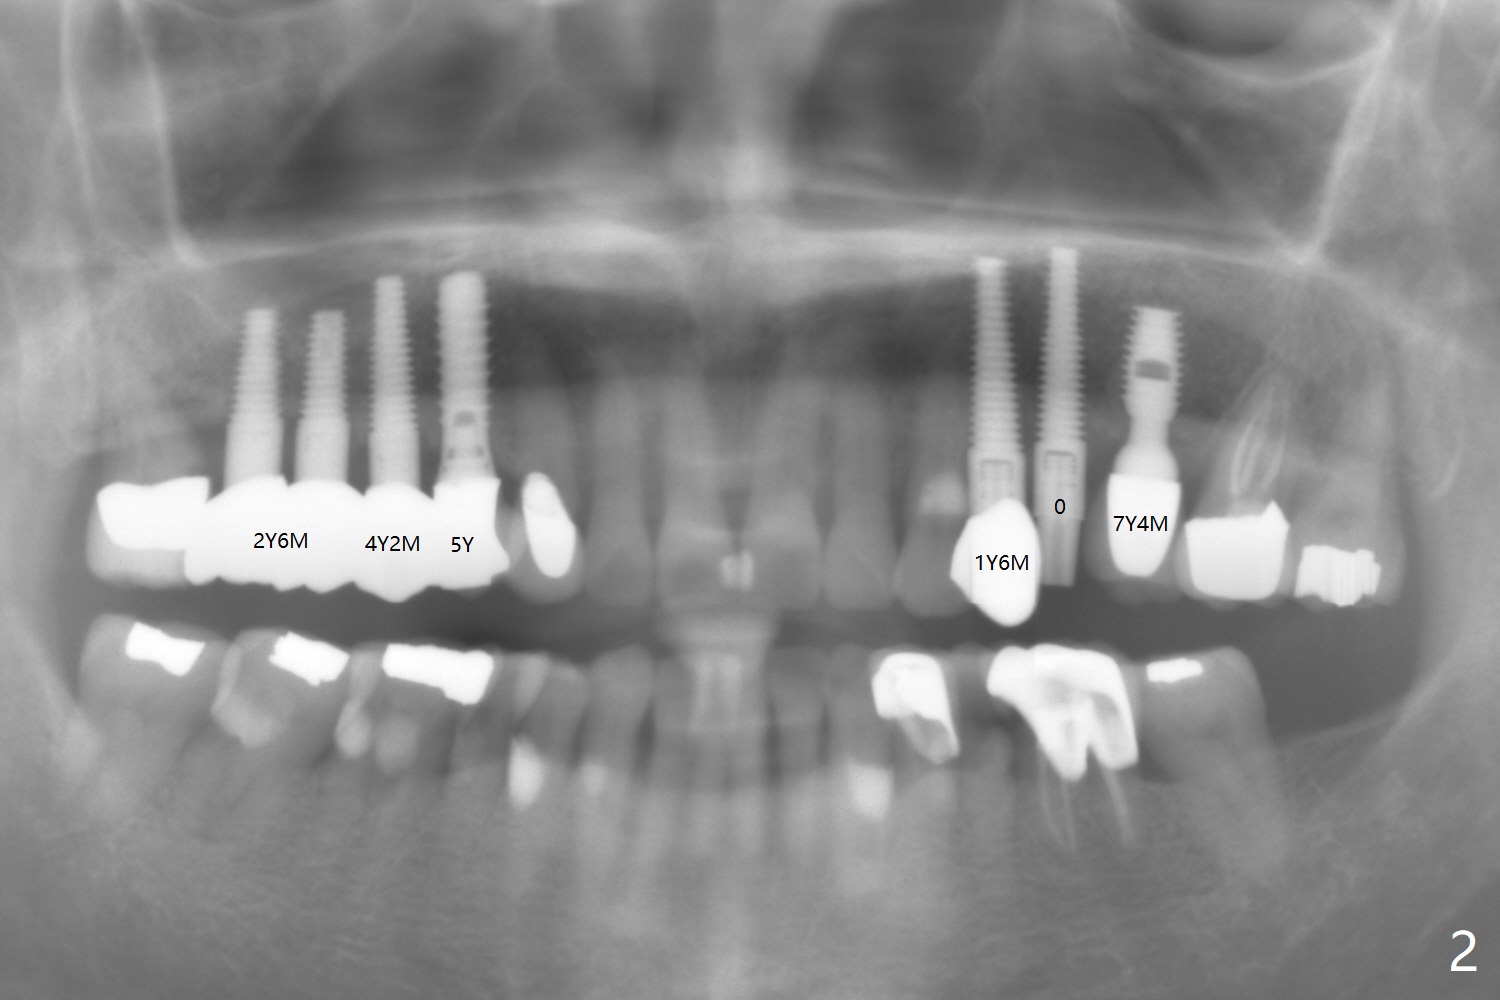

Multiple Implants for Bruxer

A 60-year-old woman appears to be a bruxer with pristine oral hygiene. There is minimal bone resorption post cementation (y: year; m: month, Fig.1,2).